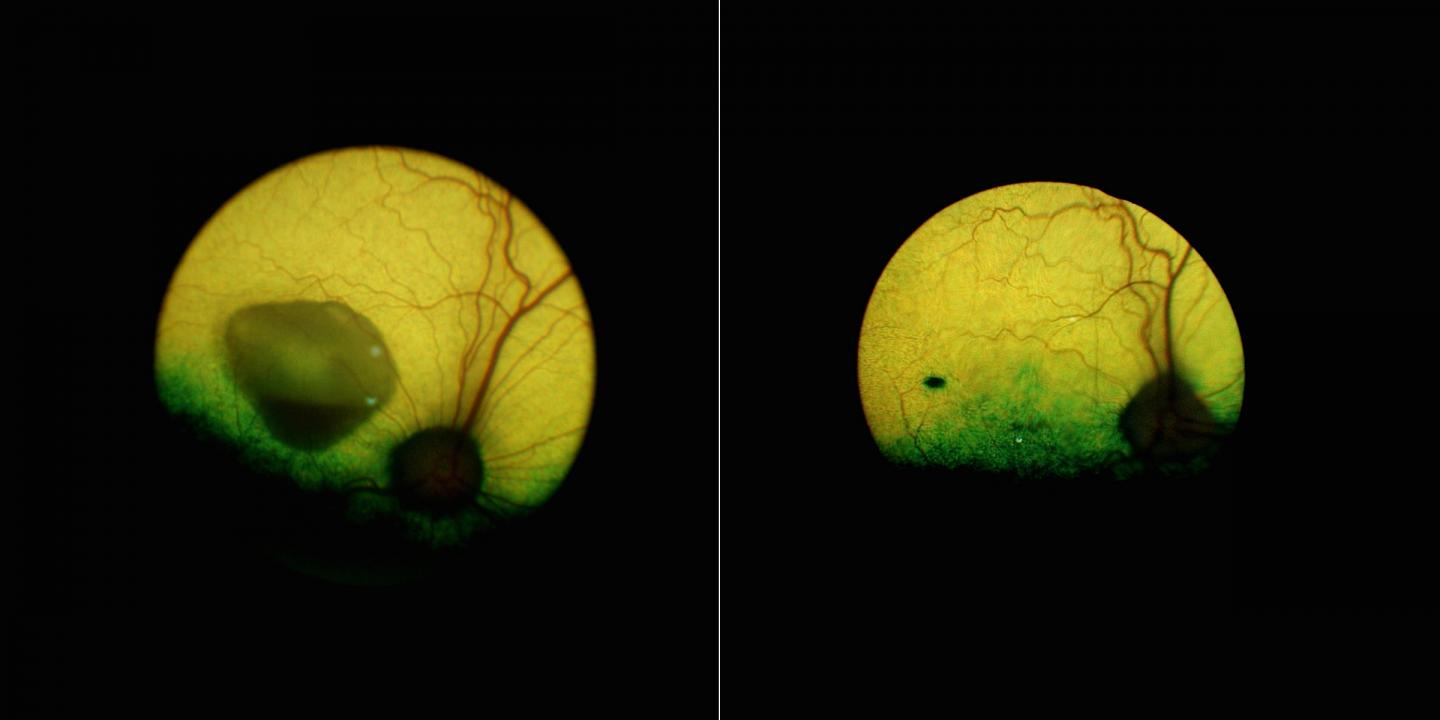

image: A view of the eye of a dog affected by the canine equivalent of Best disease before (left) and 5 years after (right) the gene therapy underscores how the treatment reversed a sizeable lesion--and lasted. The black mark visible on the treated eye is the injection site.

The therapy appears to be lasting, as the treated dogs' eyes remained disease-free for as long as five years.